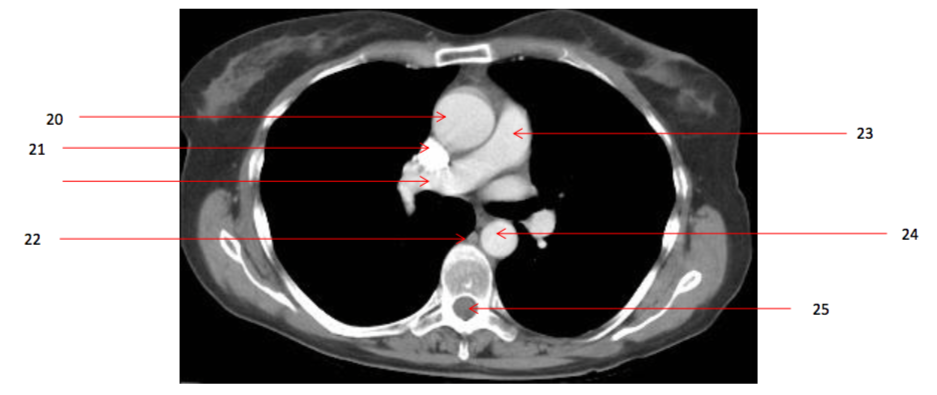

Number 20?

Ascending aorta

Number 21?

SVC

Number 22?

Azygos vein

Number 23?

Pulmonary trunk